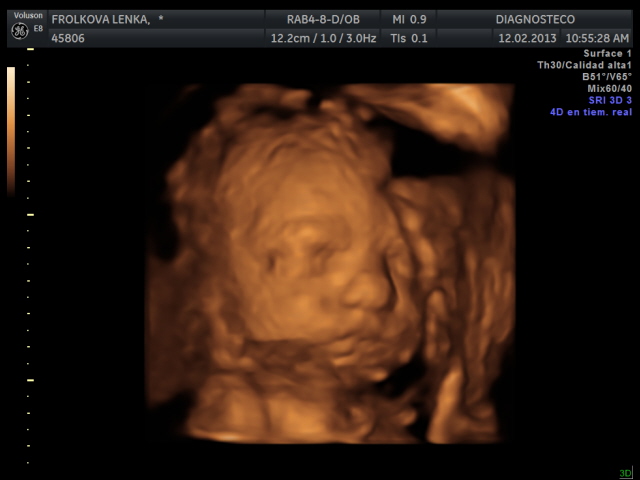

Manolito se nam vcera pretocil hlavickou nahoru a kouka na pater, takze nebyl moc videt, 4D utz zopakneme za 14 dni. Ale zatim mame nejakou tu fotecku a aji video, jen ne tak kvliatni.

Manolito uz vazi 1300 g a meri 36 cm. Ma cumacek po manzelovi a nosanek asi spis po me.

Leni Manolito je taky krásnoučkej

Krásné ráno mamušenky, no Leni.es...malej je kouzelnej